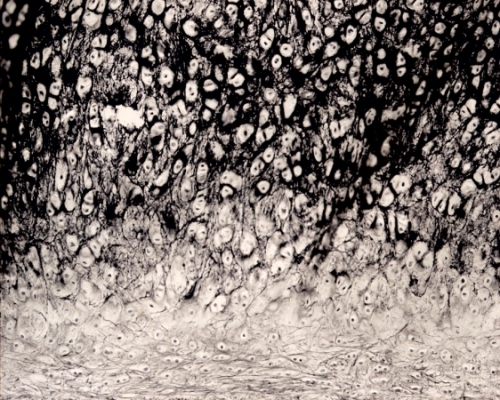

Elastic cartilage